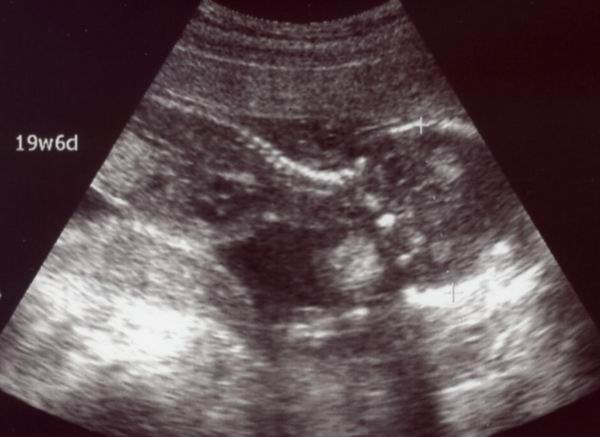

今日のベビたん。

心音がお腹の下の方で聞こえたから,「逆子かな?」と言われたけれど,

エコーで見たら正常だったみたいです。

まぁどっちにしろ今はまだ小さくて,羊水の中で自由に動ける状態だから,

逆子になってもすぐに直るし全く気にする必要はないそうですが。

右が頭(下向き)で左が胴体(上半身)。

首の骨がはっきり白く写ってますな。

そりゃ私のカルシウムも持ってかれるわけだ…

これまではCRL(頭からお尻までの長さ)を測ってたんだけど,

今回はBPD(頭の直径でいちばん長いところ)を測定。

45.8mmですって~。(画像で「+・・・・+」ってなってるところ)

まぁ順調に育ってくれてるようでほっとしました